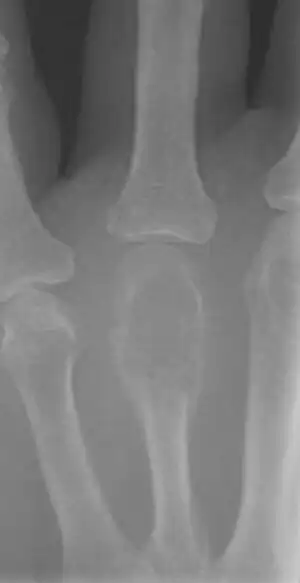

| X-ray of a giant-cell bone tumor in the head of the fourth metacarpal of the left hand | |

On X-ray, giant-cell tumors (GCTs) are lytic/lucent lesions that have an epiphyseal location and grow to the articular surface of the involved bone.[11] Radiologically the tumors may show characteristic 'soap bubble' appearance.[12] They are distinguishable from other bony tumors in that GCTs usually have a nonsclerotic and sharply defined border. About 5% of giant-cell tumors metastasize, usually to a lung, which may be benign metastasis,[13] when the diagnosis of giant-cell tumor is suspected, a chest X-ray or computed tomography may be needed. MRI can be used to assess intramedullary and soft tissue extension.